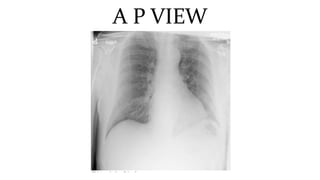

This document discusses key aspects of thorax radiology including positioning for PA and AP views, assessing heart size, visibility of anatomical structures like the scapulae, lungs zones, and measurements like cardiothoracic ratio. It provides guidance on evaluating rotation, inspiration, and penetration on chest x-rays as well as identifying structures like the lobe of azygos vein and aortic knuckle.